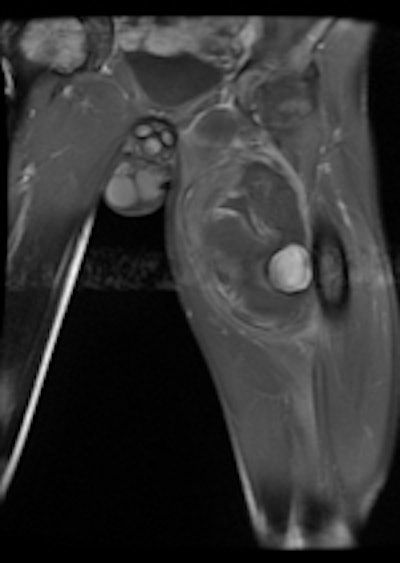

A 19-year-old male with delayed presentation following gunshot injury in the thigh. Left: T1 coronal MRI shows a large pseudoaneurysm in the upper thigh. Pre- (middle) and postembolization (right) angiographic images demonstrate successful treatment of the pseudoaneurysm.The two mechanisms of tissue injury that account for the majority of damage caused by a bullet are direct crushing of tissue by the projectile (causing a permanent cavity) and temporary cavitation, which stretches and tears surrounding tissues. Increased velocity, fragmentation, deformation, and rolling/spinning of the bullet will cause more damage by both these mechanisms, he pointed out.